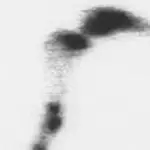

Figure 3C. A bone scan was positive in the shaft of the tibia and was suggestive of a hairline stress fracture.